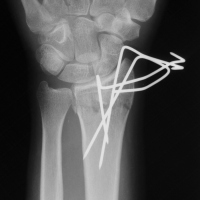

| Case 6 Extraarticular distal radius fracture with angulation and dorsal comminution. |

| Attempts at

closed reduction alone were unsuccessful. |

| Freer elevator

introduced percutaneously as a reduction aid. |

| Percutaneous

fracture stabilization with three pins via the

dorsal radial tubercle, radial styloid and FCR

portals. |

| Pins were left

protruding and bent to overlap. |

| Thermoplastic-pin

construct at 6 weeks, immediately prior to removal. |

| Late result. |